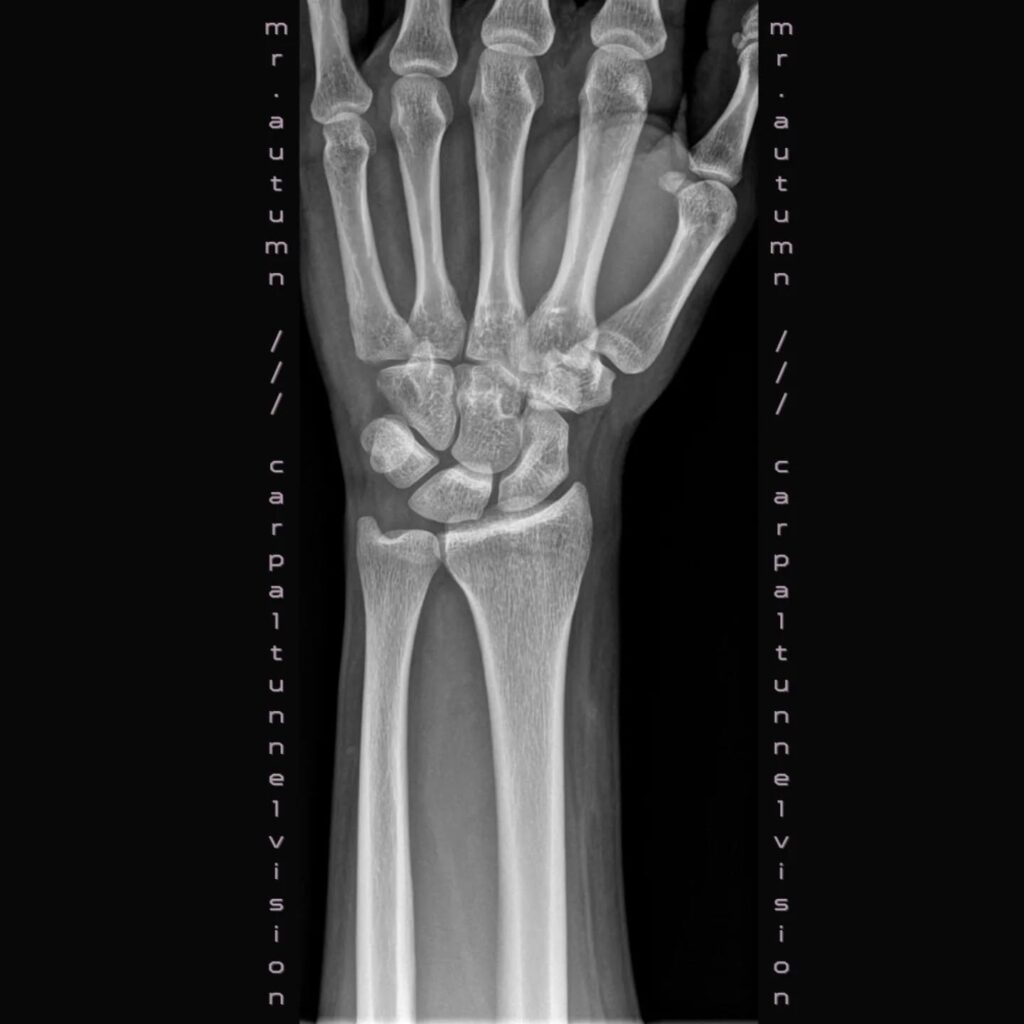

De Gentse singer-songwriter Pieter Angel D’Haeseleer kreeg in 2023 pijn in zijn pols: “Ik vreesde dat ik nooit meer gitaar ging kunnen spelen zoals voordien. Na een hele periode van echo’s, MR-scans, MRI’s en kinesitherapie kwam er nooit een conclusie wat de eigenlijke schade was. Meer zelfs, er is nooit schade aan mijn pols teruggevonden. Omdat muziek maken een spirituele noodzaak is, besloot ik om een elektronische ep te maken. Het is waarschijnlijk geen werk dat ik ooit live zal brengen, maar ik ben wel blij dat ik het met de wereld kan delen!”

De eerste, instrumentale, track kreeg de titel Carpal Tunnel Vision: “De titel verwijst naar een gegokte diagnose die ikzelf maakte. Iets ambigu en liminaal. Daarom dat ik de eerste track wilde baseren op hedendaagse ambient muziek zoals die van Øneheart, maar ook lichtjes gebaseerd op Sigur Ros‘ naamloze album ().” De ambiguïteit wordt weerspiegelt in reflecterende toetsen, die weerkaatsen in een bitterzoet trage ambient soundscape. Backing vocals die een beetje doen denken aan Gregoriaanse zang. Verhelderend mooi.